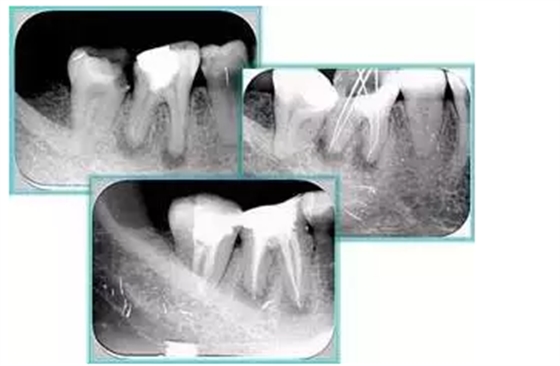

7. 器械折斷

右圖及下圖為器械折斷的 X 線片。箭頭處示折斷器械。

解決方法: ( 1 )取出。 ( 2 )通過。 ( 3 )重新確定工作長(zhǎng)度,充填。 ( 4 )根尖手術(shù)。

器械折斷可以不用取出,取出的原因多是患者心理因素。留在里面的器械關(guān)鍵是進(jìn)行消毒,預(yù)防性使用抗感染藥物,預(yù)防感染。

二、臺(tái)階

定義:根管內(nèi)壁上人為產(chǎn)生的不規(guī)則形狀阻止器械順利進(jìn)入根尖。

原因:器械沒有預(yù)彎,根向壓力過大。

右圖箭頭處示臺(tái)階形成。

解決方法: ( 1 )器械預(yù)彎。 ( 2 )若出現(xiàn)銼的螺紋擰緊,立即換用小號(hào)銼。 ( 3 )一旦到達(dá)WL,即按照從小到大順序預(yù)備根管。 ( 4 ) H銼幫助提高切割效率。